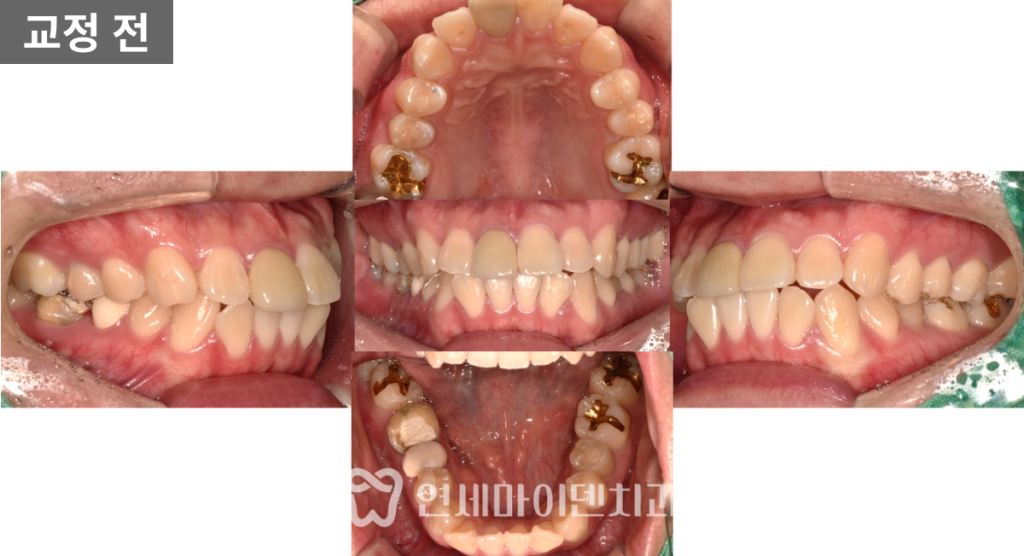

초기 검사 결과,

앞니가 전반적으로 앞으로 뻐드러져 있었고

일부 치아는 신경치료가 불완전하거나

염증이 동반된 상태였습니다.

또한 골격적으로는

위턱이 상대적으로 발달하고

아래턱이 뒤로 들어간

2급 부정교합 양상을 보이고 있었습니다.

이번 케이스는 단순히

돌출입 치열 문제만 있는 상황이 아니라,

몇몇 치아 자체의 예후가 좋지 않았기 때문에

조금 더 신중한 발치 교정 계획이 필요했습니다.